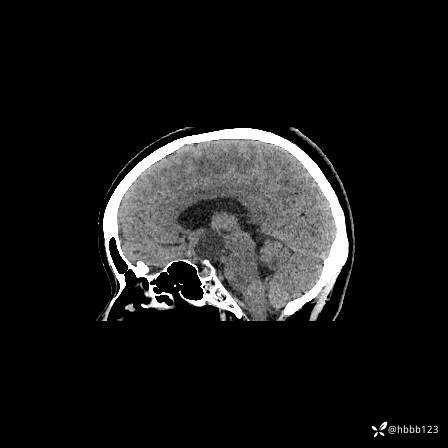

矢状位重建: